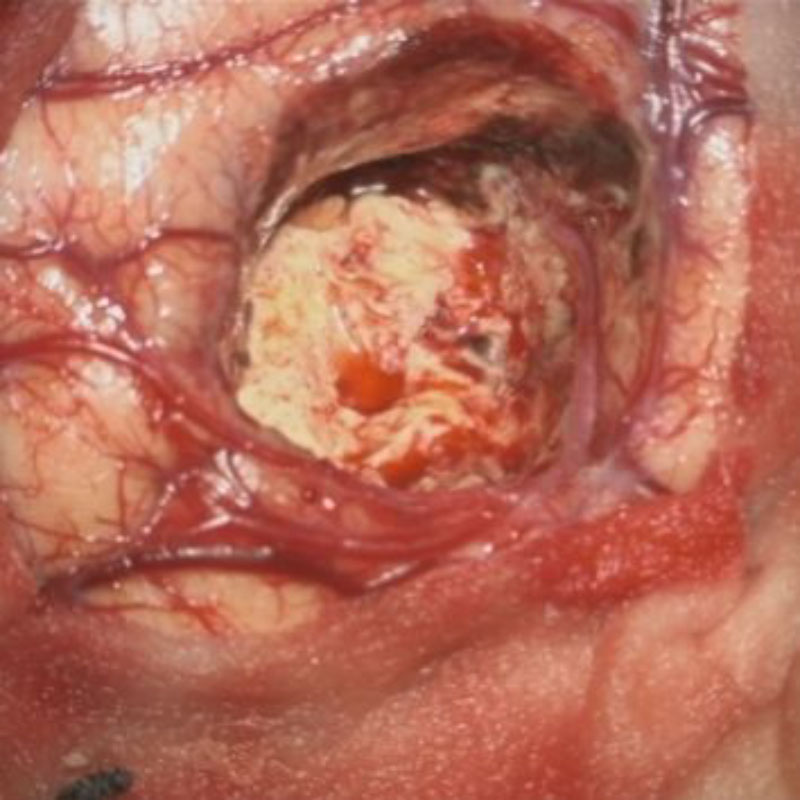

良性頭蓋咽頭腫

頭蓋内腫瘍摘出術

No.’25_113 摘出 前

No.’25_113  摘出 中

No.’25_113 摘出 後